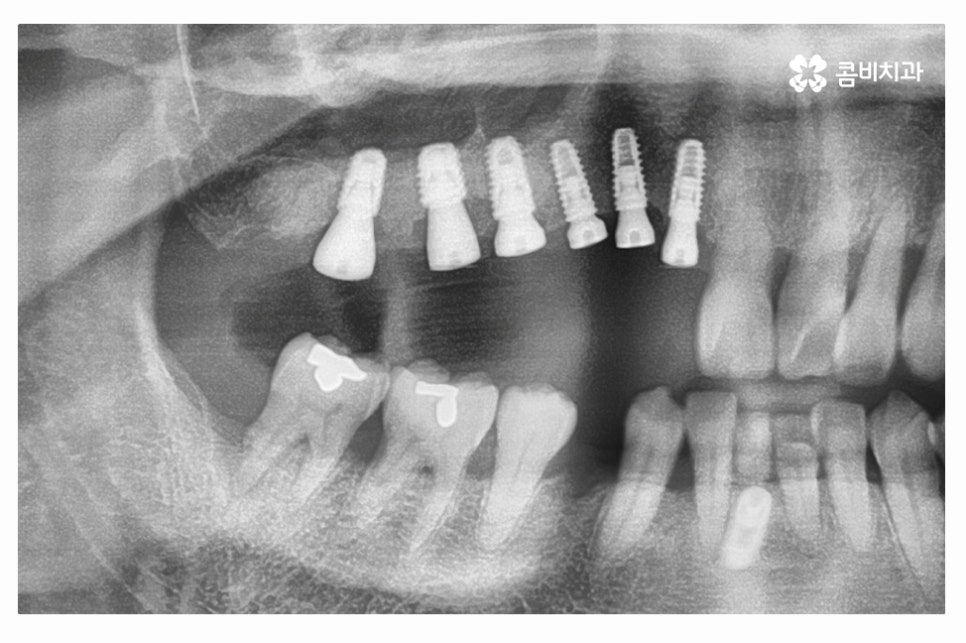

임플란트의 구성을 살펴보면 치아를 발치한 후에는 임플란트의

인공치근을 심게 되며(사진에서 좌측), 인공치근에

지대주(사진에서 우측)를 연결한 후에 지대주에 보철물을 연결하게 되며

임플란트가 단단하게 고정되기 위해서는 잇몸 뼈와

인공치근의 골 유착 과정을 건강하게 거쳐야 할 필요가 있어요.

우측 사진의 경우 힐링어버트먼트를 장착한 모습인데, 일반적으로는

1차 수술을 마치고 약 1개월 정도 후 임플란트 어버트먼트가 들어가기 전에

어버트먼트가 잘 들어갈 수 있도록 잇몸의 모양을 잡아 주기 위해 장착을 하며,

잇몸뼈가 건강하고, 식립이 잘 되었다면 1차 수술을 하면서 바로

힐링어버트먼트를 장착하는 경우도 있지만, 정석은 2차 수술 때 장착을 하는 경우라고 할 수 있어요.